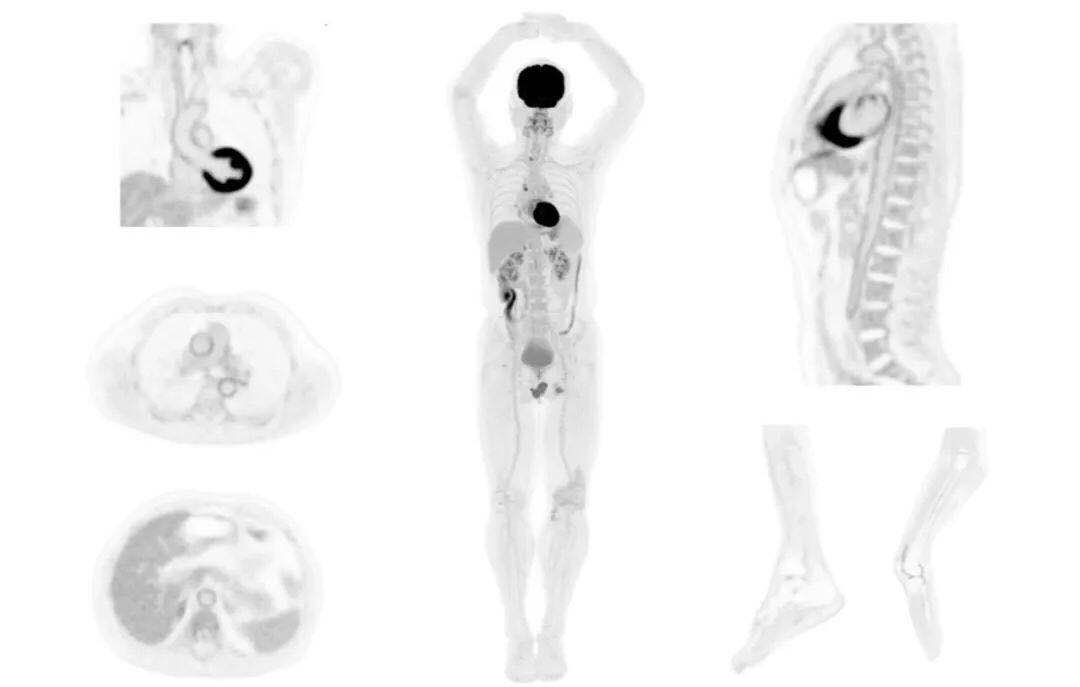

圖例

直腸癌

男,45歲,直腸癌術(shù)后9個月,發(fā)現(xiàn)肺占位

臨床診斷:直腸區(qū)術(shù)后改變,復(fù)發(fā)伴骶骨受累,雙肺多發(fā)轉(zhuǎn)移

肺癌轉(zhuǎn)移及復(fù)發(fā)

患者男性,66歲,七年前發(fā)現(xiàn)右肺肺癌,其間手術(shù)兩次,共切除兩個肺葉,復(fù)查;

診斷意見,回腸轉(zhuǎn)移,右肺殘留部復(fù)發(fā)